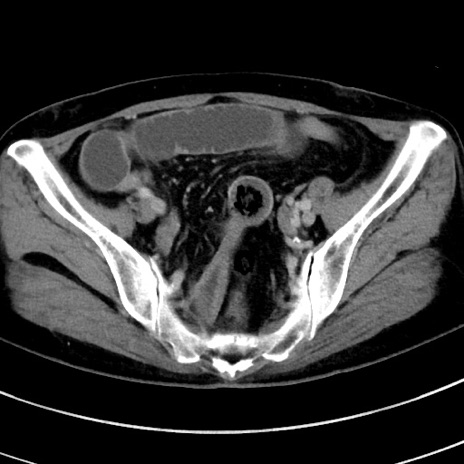

冠状断像

【症例】 60歳代女性

【主訴】むかつき、みぞおちの痛み

【現病歴】3日前よりむかつきがあり、食事がとれない。

【既往歴】糖尿病

【身体所見】発熱なし、心窩部圧痛軽度あるも、腹膜刺激症状なし。

【データ】WBC 7400、CRP 1.92